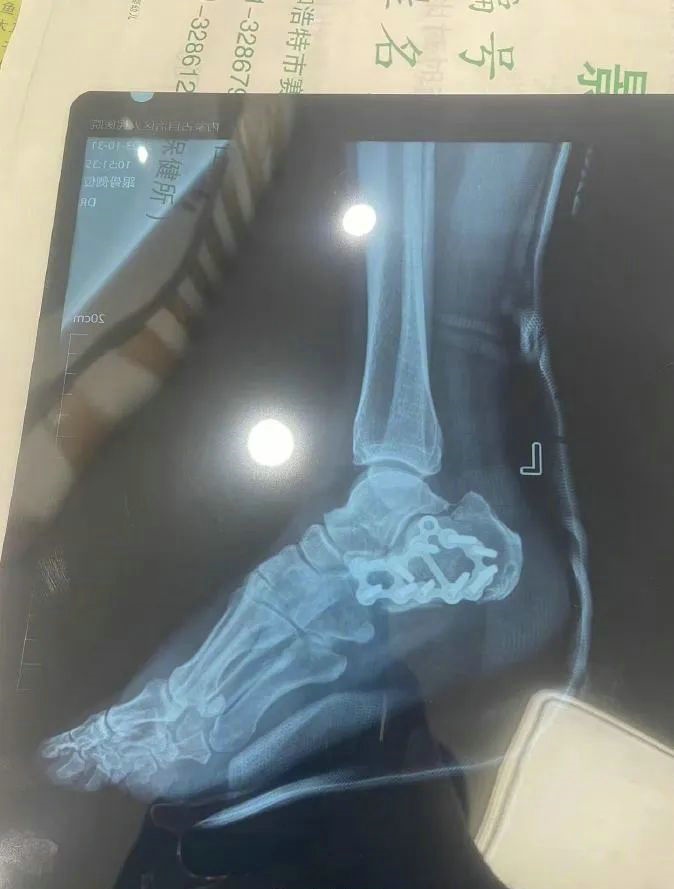

“那時候我剛工作了兩天,在第三天10月22日下午施工過程中從三層高的鐵架上摔了下來,導(dǎo)致30厘米左右的鋼筋刺穿我的右側(cè)臀部,左腳跟也粉碎性骨折,被送往內(nèi)蒙古自治區(qū)人民醫(yī)院救治,當(dāng)晚做了手術(shù)取出刺在右臀部的鋼筋,10月30日又進(jìn)行了左腳粉碎性骨折手術(shù)。”雷先生告訴記者。